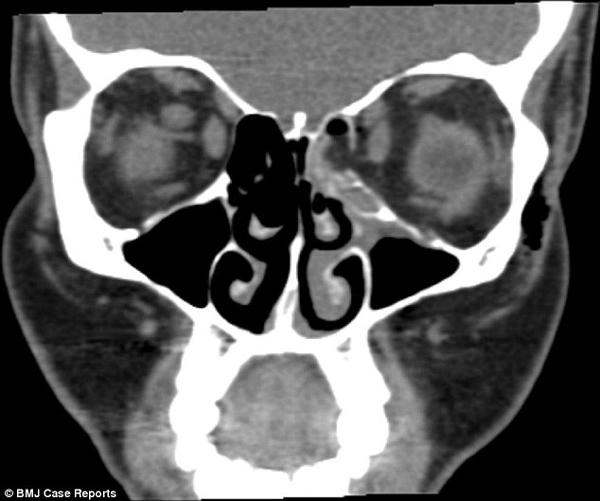

Tại Bệnh viện Đại học North Middlesex, sau khi chụp chiếu và khám kỹ lưỡng, các bác sĩ chẩn đoán cô bị gãy xương trong mắt trái và đây là một thương tích rất hiếm khi xảy ra. Mặc dù tầm nhìn của cô bị suy giảm và xương mắt bị gãy nhưng may mắn các chuyển động và bộ phận khác vẫn bình thường.

Các chất nhầy chảy tràn vào mũi bên trái tạo thành khoảng đen trên phim chụp.

Lý giải về nguyên nhân khiến cho người phụ nữ bị gãy xương trong ổ mắt, Tiến sĩ Sam Myers, bác sĩ tại Bệnh viện Đại học North Middlesex cho biết khi xì mũi, người phụ nữ đã vô tình làm tăng áp lực trong xoang khiến xương bị gãy. Đồng thời chính điều này đã khiến cho các chất nhầy rò rỉ vào đường hô hấp và trong mô quanh mắt.